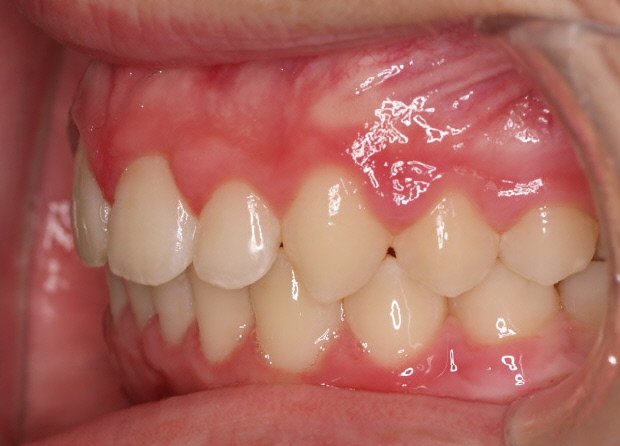

- Realizar un tratamiento ortodóncico para mover los dientes y cerrar el diastema.

Si su frenillo labial es demasiado grande, puede que le remitan a un especialista para someterse a un procedimiento quirúrgico llamado frenectomía. Este procedimiento consiste en cortar el frenillo y volverlo a colocar para permitir que tenga más flexibilidad. Cuando la frenectomía se realiza en un niño, el espacio puede llegar a cerrarse por sí solo. Si se trata de un adolescente o un adulto, puede que sea necesario cerrarlo con ortodoncia. Es esencial acudir al dentista para saber cuál de estas opciones es la adecuada en su caso.